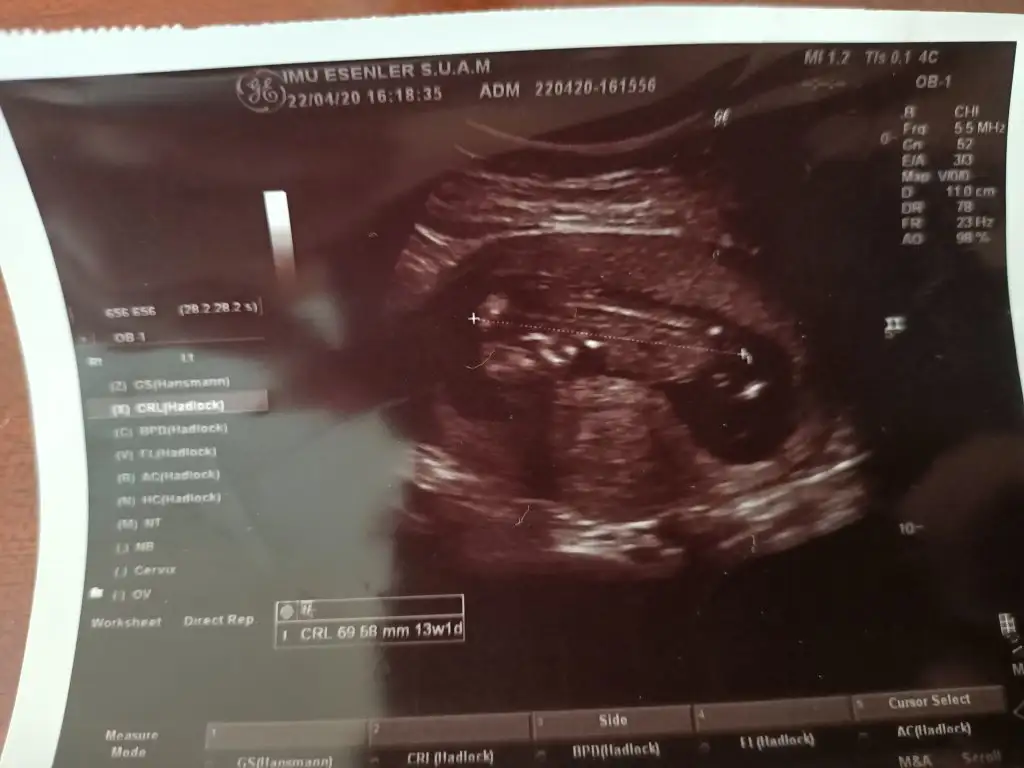

Merhabalar anlayanlar benim görüntülerede bakabilirmi 13 haftalık olduk merak ediyorum 😉

Eklentiler

• IMG20200423112010.webp

IMG20200423112010.webp

25,9 KB · Görüntüleme: 54